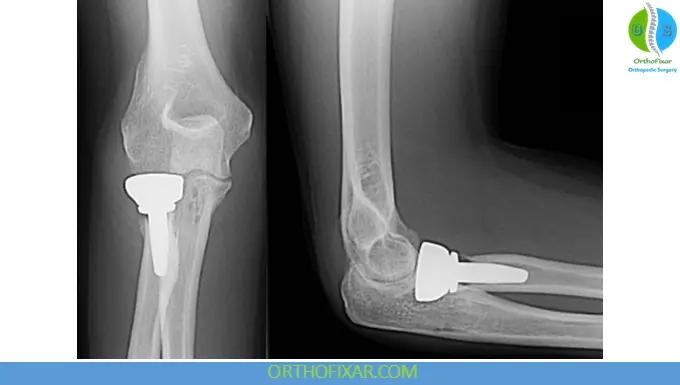

2. Radial Head Replacement

Indications:

- Comminuted fractures (Type III)

- Unstable elbow or forearm injuries

Notes:

- Metallic prostheses (titanium/vitallium) preferred

- Avoid oversizing, which can impair joint mechanics